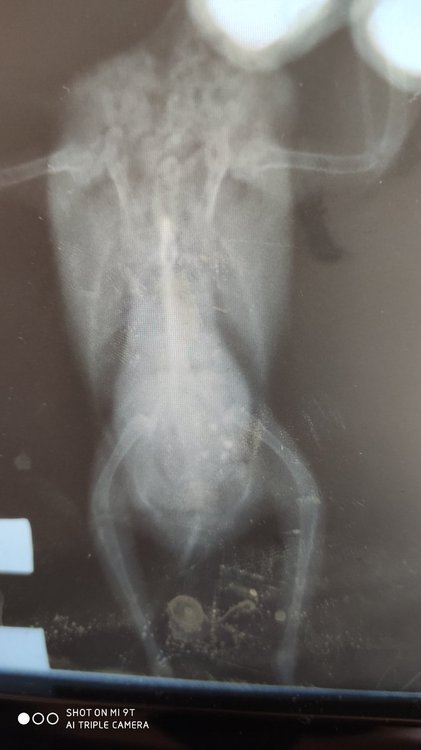

4. Какие симптомы и подробно, что случилось? В начале года сильно набирал вес (52-56 грамм), не могли похудеть, стал очень нервным, в марте неудачно упал, потерял зрение, по рентгену было видно увеличенную печень, которая давит на желудок и воздушные мешки, помет был в норме, пьем мелоксивет и габапентин постоянно, было 2 курса по месяцу Укрлива для печени, 1 курс карсила. Во время второго курса Укрлива начал какать с водой. Думали морковка плохая попалась, давали Энтеросгель отдельно от других лекарств, позже увидели, что пьет очень много воды. Изначально подумали что от голода/жадности (у него повышенный аппетит, кормили 2 ч. ложки на 7-8 приемов каждые 2 часа, 1-2раза из которых ночью). сделала глюкотест мочи - повышена.  Опускает крылья, правое ниже левого. Когда сидит скрещивает их под хвостом, когда ходит - нормально держит. Голова преимущественно наклонена влево, иногда ровно держит

Последний рентген показал ещё большее увеличение печени и почки неправильной формы. Анализ крови на глюказу -норма, мочевая кислота понижена.

Может есть ещё шансы как-то помочь ему. Рентген плёночный, засунула влажным в файл и он местами пожелтел, к сожалению. Первые два снимка - март, второй - 2 июня

К сожалению, в этой клинике рентген плёночный и для мелких птиц малоинформативен...